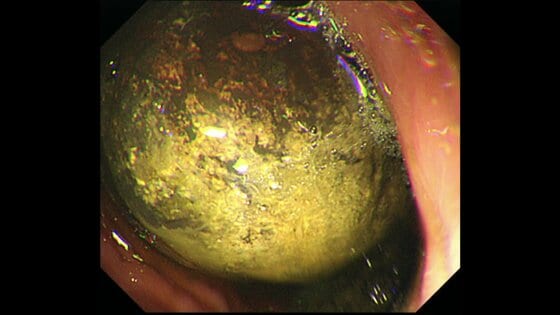

胃に5cm大の石!?食べすぎ注意 秋の味覚「柿」が柿胃石の要… ギャラリー 1/8 記事に戻る 2/8 記事に戻る 3/8 記事に戻る 4/8 記事に戻る 砕かれた柿胃石 5/8 記事に戻る 6/8 記事に戻る 7/8 記事に戻る 8/8 記事に戻る